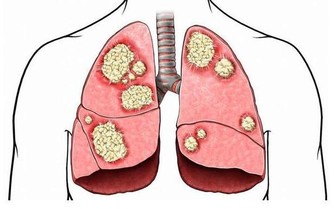

癌症一般是指惡性腫瘤,腫瘤是指機體在各種致瘤因子的作用下,局部細胞組織增生所形成的新組織。它有一個特點,它的生長不受正常機體的生理調節,而是破壞正常的組織和器官。我們所謂的癌症,也就是惡性腫瘤和良性腫瘤相比,具有以下幾個特徵。第一個是生長速度,第二個是容易發生轉移,特別是發生轉移以後,腫瘤的危險性就大大地增加。第三,容易復發。第四,復發最終會導致患者多髒器受損,最終導致患者死亡。